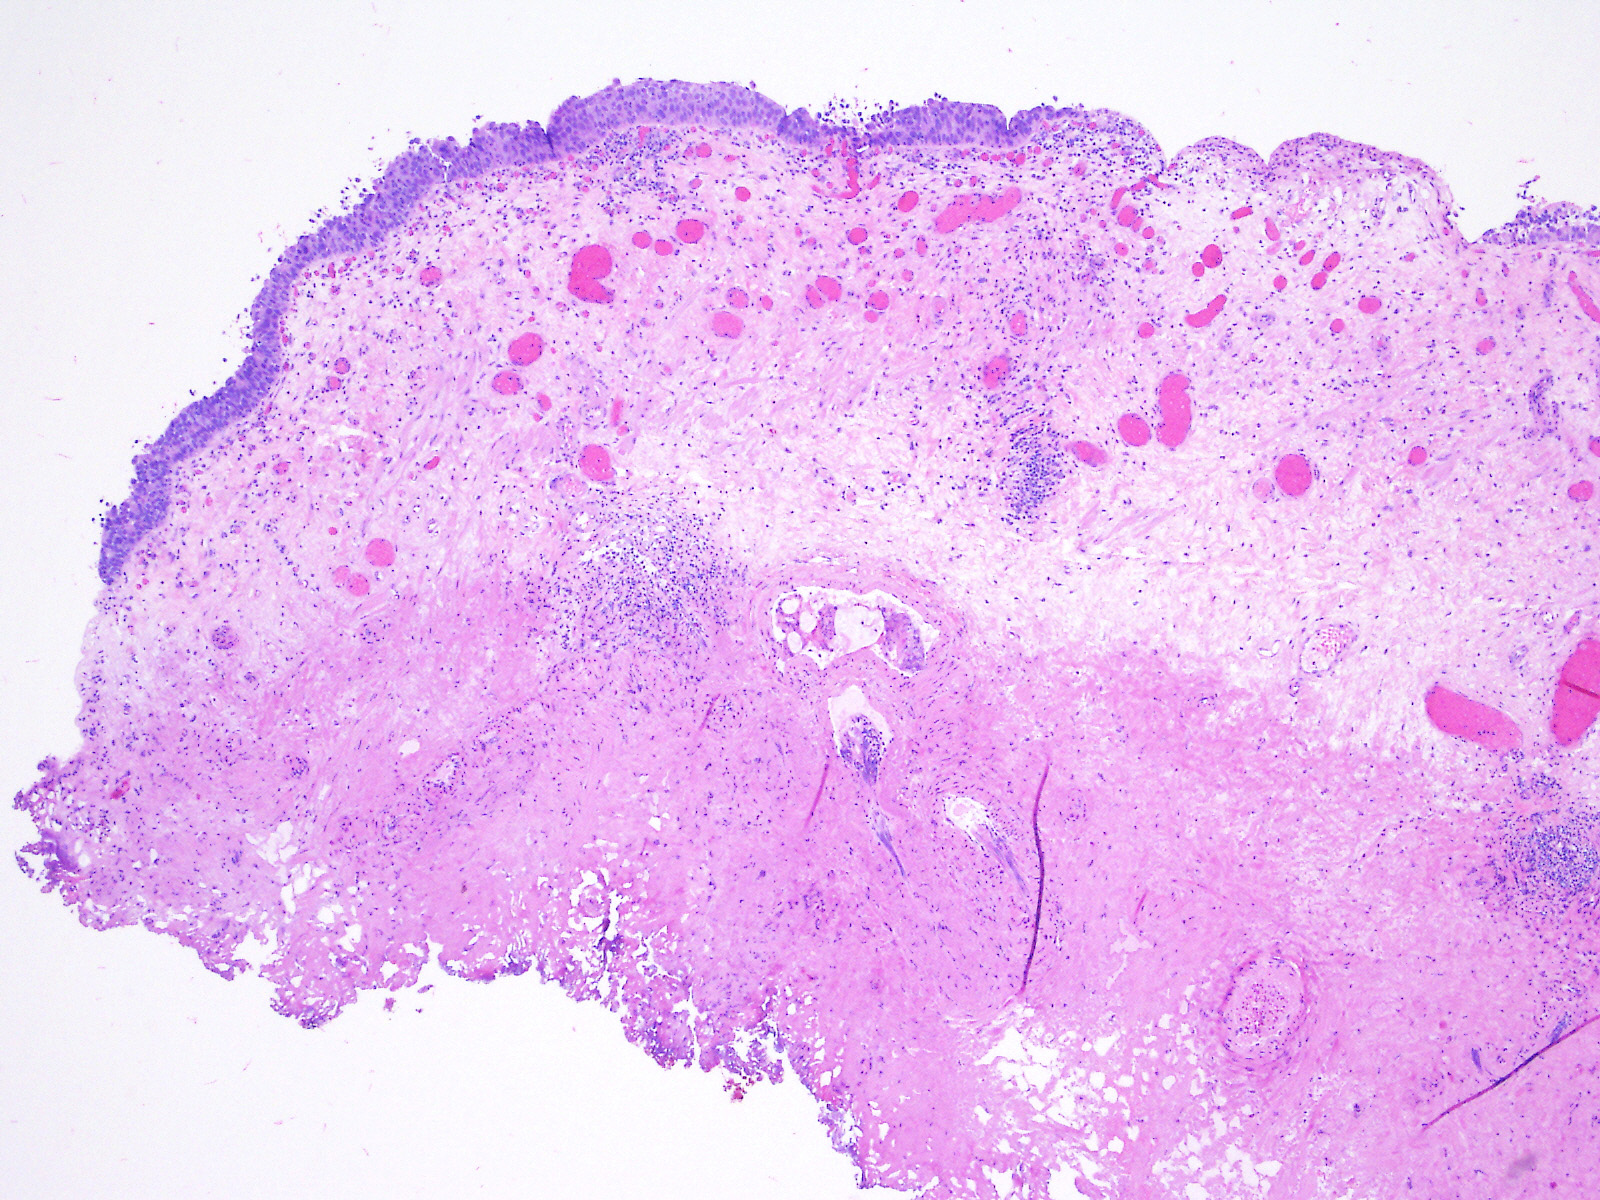

Consensus grade: Carcinoma in situ (CIS)

Case description (by case creator):

A 49-year-old man underwent a 2nd look bladder cystoscopy and TUR of a prior biopsy site.